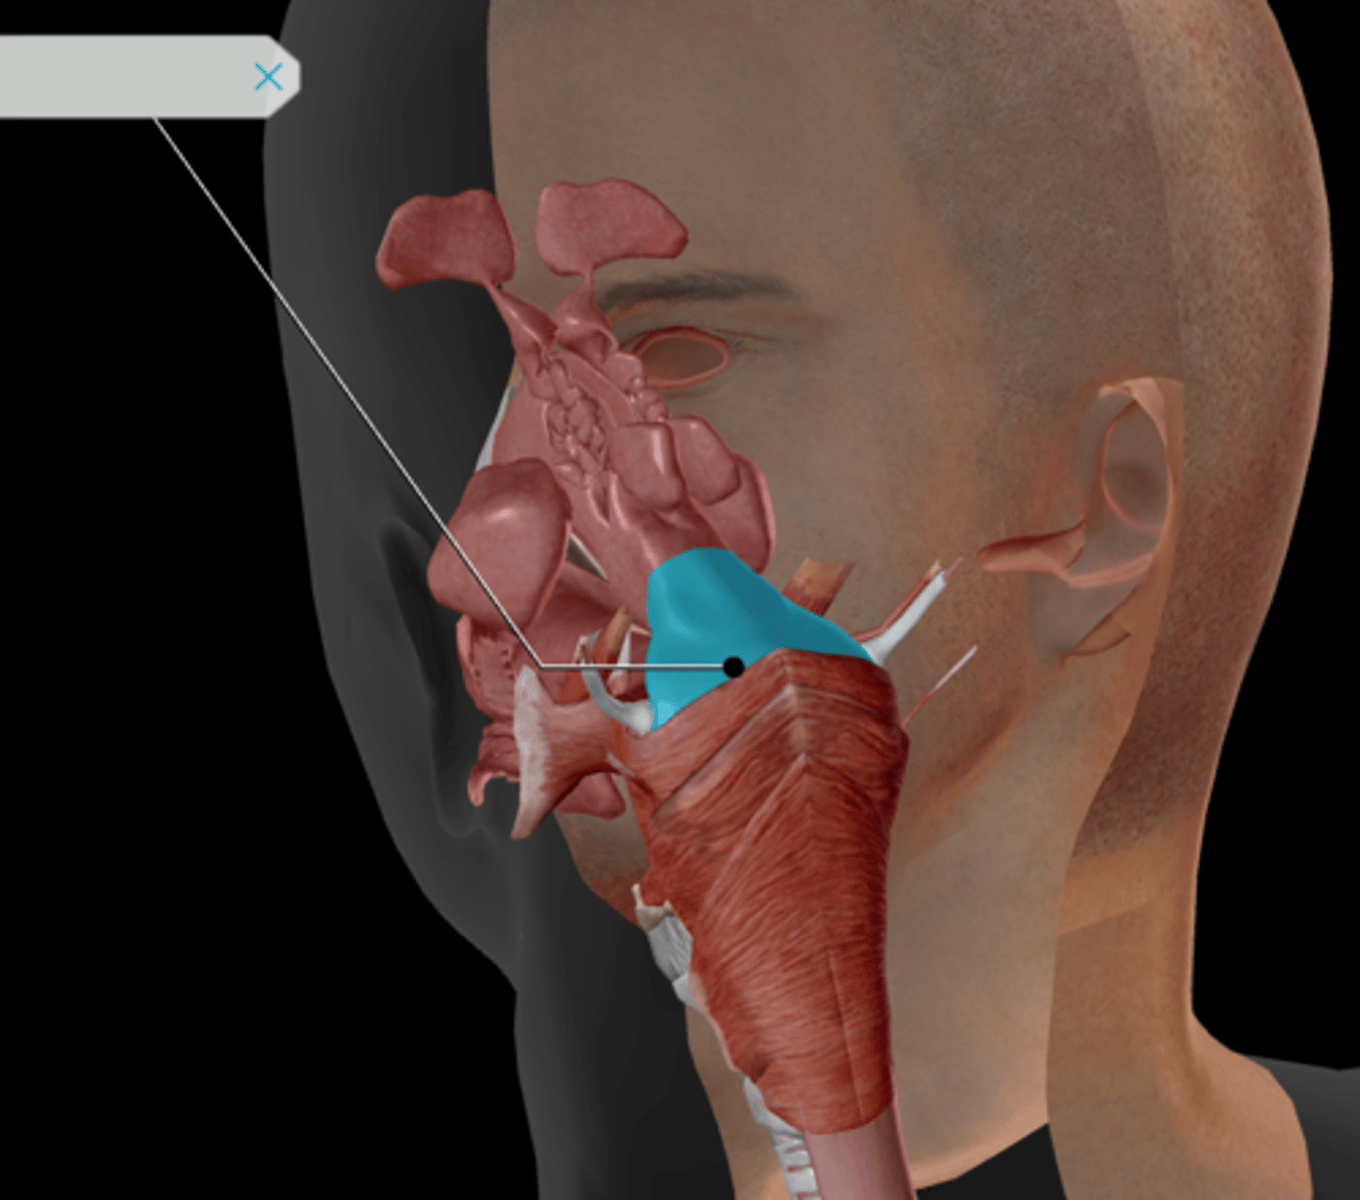

Nasopharynx

Oropharynx

Laryngopharynx

Larynx

Epiglottis